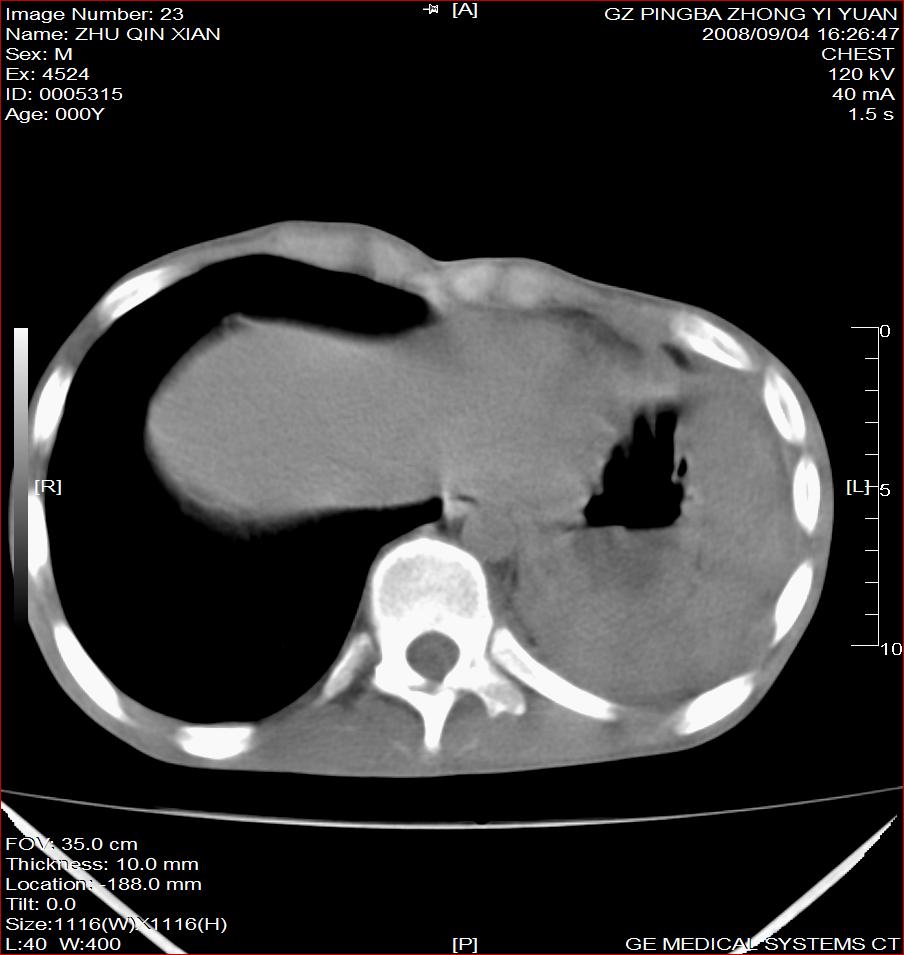

以下是引用随光逐影在2008-9-4 20:05:00的发言:[br]1)考虑两肺结核。2)左侧胸膜炎(胸膜肥厚、粘连,胸腔积液)。3)左侧局限性气胸。

以下是引用子十在2008-9-4 19:34:00的发言:[br]左上肺结核并空洞及双肺播散。节段性肺不张、胸腔积液、胸膜肥厚粘连。[br]